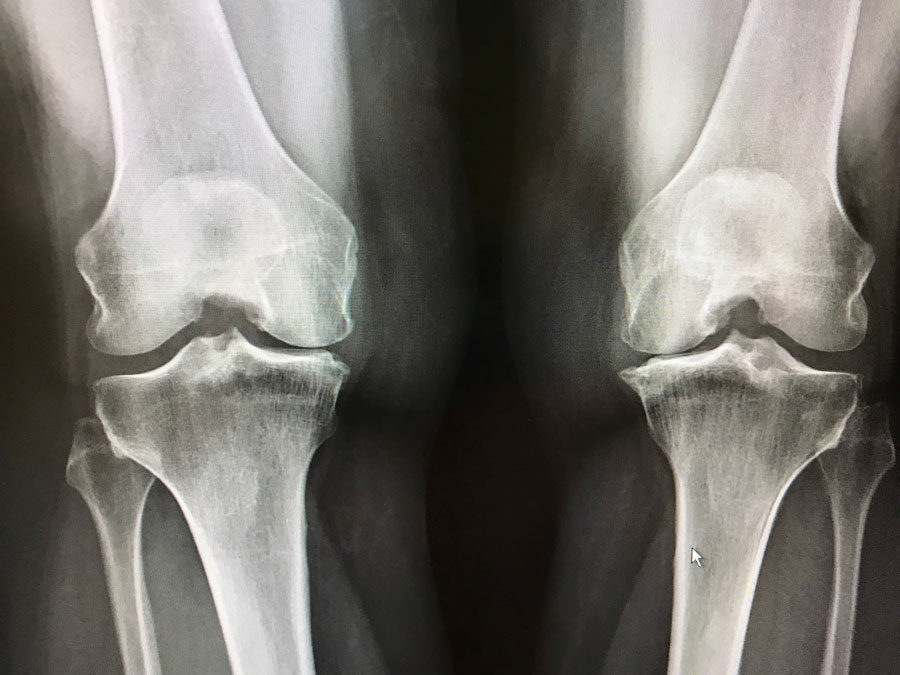

Las personas con osteoartrosis tuvieron mayores tasas de consultas de médicos de cabecera, ingresos hospitalarios y mortalidad por todas las causas que variaron entre los sitios conjuntos. Br J Gen Pract,, 10 de julio de 2023